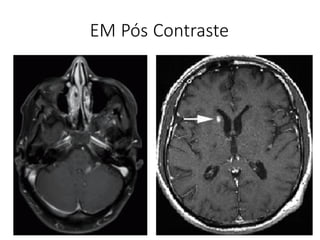

EM Pós Contraste